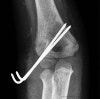

X-ray : 외과 골절(Lateral condyle fracture)

전위 골절인 경우 수술적 치료 후 조기 관절 운동 시행이 일반적 치료 원칙입니다.

Stage 2 : 도수적 정복 및 경피적 핀 고정술을 시행합니다. 관절면을 완전히 정복해야 합니다.